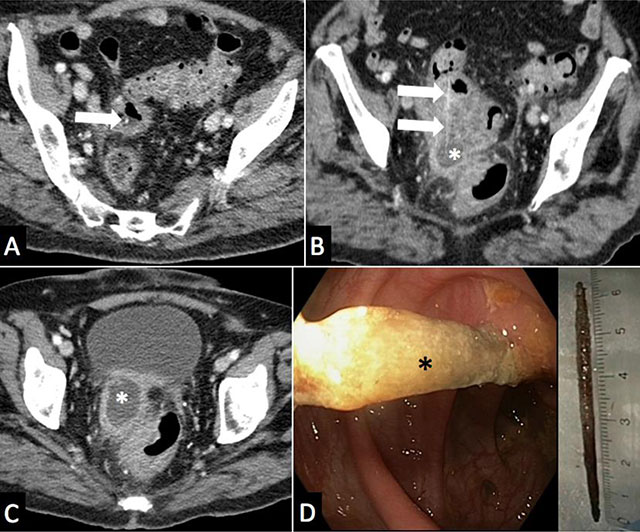

A 79-year-old woman presented to the emergency room with a month history of intermittent hypogastric abdominal pain and fever. Past medical history included diabetes and diverticular colic disease. CT scan with intravenous contrast medium (Figure 1A, B, C) demonstrated a colic diverticulosis with sigmoid wall thickening, extra-digestive abscess of 4.5 cm in diameter (white asterisk), adjacent fat stranding and a 60 mm long, 2 mm thick high density linear structure (arrow) coursing through the colic wall and the abscess. Covered colic perforation and an extra-digestive abscess related to a wooden toothpick were suspected. After antibiotherapy, recto-sigmoidoscopy (Figure 1D) was able to confirm and retrieve the wooden toothpick (black asterisk) embedded through the colic wall. Clinical follow-up was favorable.

Figure 1